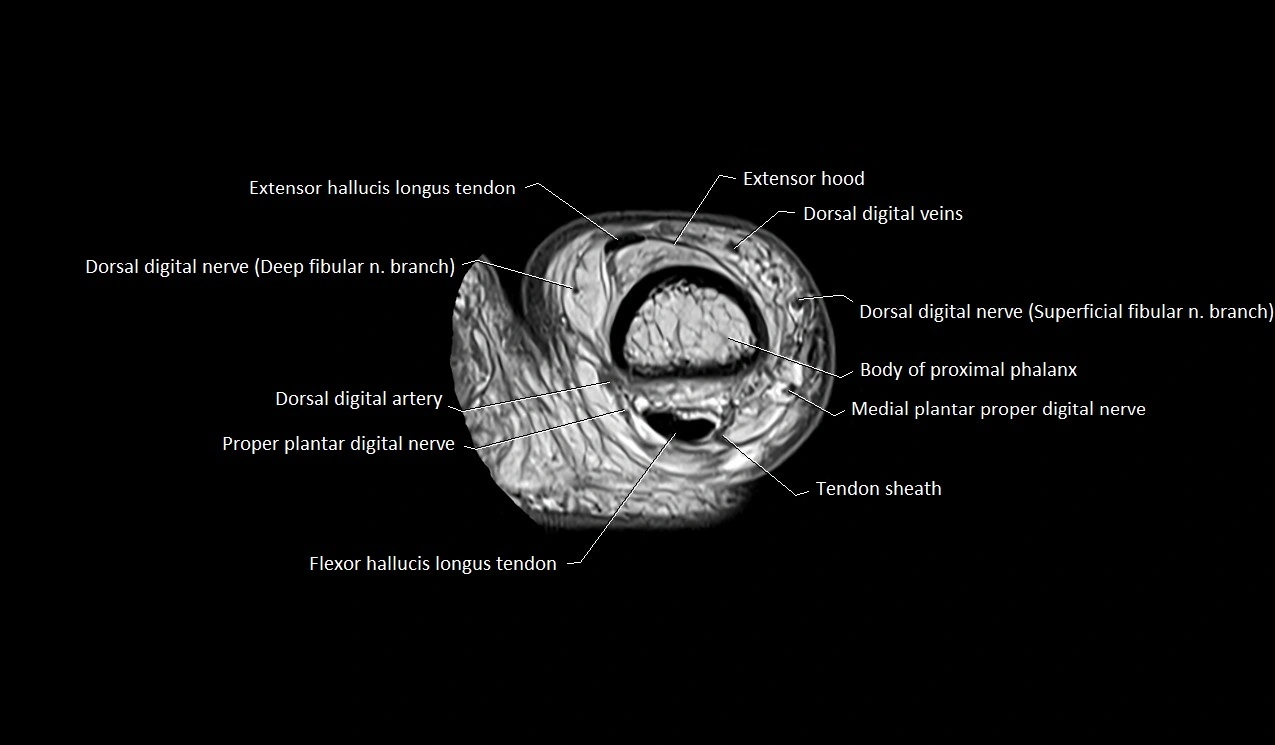

MRI image

image